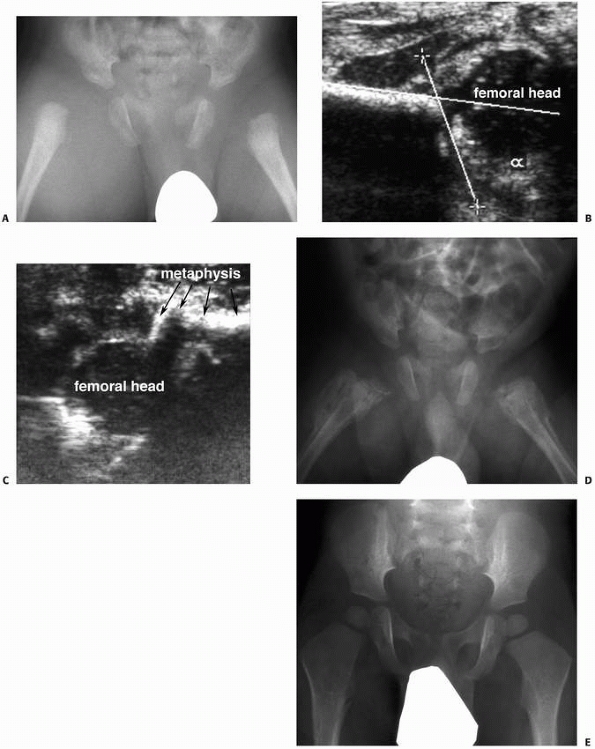

assess the congruency of articular surfaces. Arthrography may help

ossification centers in the epiphyses.6,44,63,95,145 Ultrasonography is occasionally useful for diagnostic purposes to identify epiphyseal separation in infants (Fig. 5-30).29,44,45,47,69

| Figure 5-30 Ultrasonography can be useful as a noninvasive investigation confirming intra-articular effusion or epiphyseal separation, particularly in infants. A. Anteroposterior radiograph of a 2-month-old infant with bilateral hip pain and generalized irritability. Septic arthritis is included in the differential diagnosis. B. Ultrasonographic image of the right hip demonstrates a femoral head contained in the acetabulum, without significant hip effusion. C. This ultrasonographic image demonstrates separation of the proximal epiphysis from the femoral metaphysis. The diagnosis is nonaccidental trauma. D. One month later, radiograph demonstrates extensive periosteal reaction bilaterally. E. At 18 months of age, radiograph demonstrates remarkable remodeling, without evidence of physeal growth disturbance or epiphyseal abnormality. |